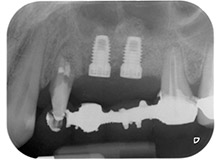

Fig. 2 e 3: Dopo aver sollevato i lembi, un mese dopo il pretrattamento endodontico e l'inizio della terapia periodontale sull'intera dentatura, la radice buccale del dente 24 mostrava una perdita totale di tessuto osseo e di punti di attacco.

Un mese più tardi, nel giorno programmato per l'intervento, il dolore e l'infiammazione in corrispondenza del dente 24 erano minimi, ma era ancora presente mobilità di classe 2 secondo Miller. Dopo l'apertura dei lembi e la pulizia del tessuto periapicale e periradicolare infetto, l'estensione della mancanza ossea si è resa evidente (Figg. 2 e 3).

Tutto il tessuto osseo vestibolare e distale era mancante in corrispondenza della radice buccale. La possibilità di attacco era essenzialmente ristretta alla radice palatale, evidenziando la prognosi negativa preliminare. Anche il dente 27 mostrava un punto di attacco orizzontale ridotto e una rarefazione apicale minima (cfr. Fig. 1), senza sintomi clinici.